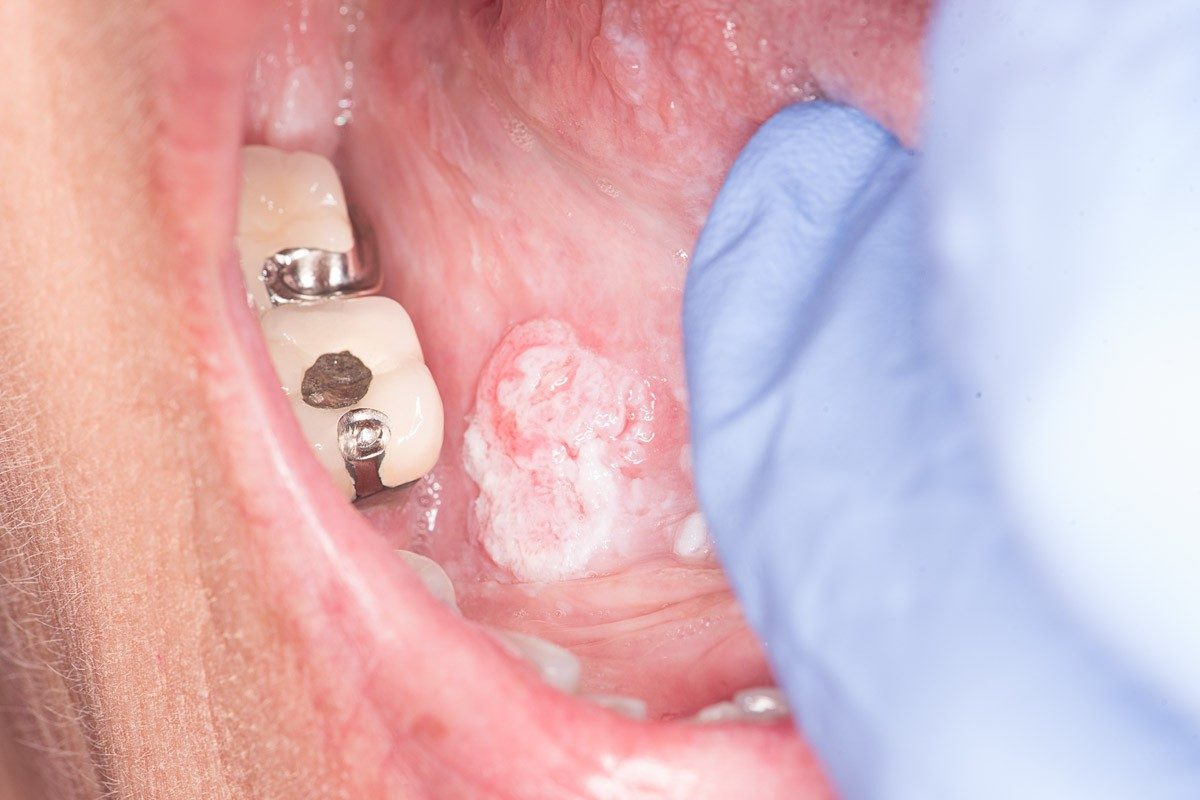

Many patients ignore persistent mouth ulcers, red or white patches, and unexplained lumps, assuming they are harmless. This delay allows abnormal cells to grow silently. By the time severe symptoms such as difficulty swallowing or chronic pain appear, the disease may already be advanced.

Symptoms That May Indicate Disease Progression

Certain symptoms suggest that oral cancer may be advancing, including:

- Persistent or worsening mouth pain

- Enlarging lumps in the neck or jaw

- Difficulty opening the mouth or chewing

- Sudden weight loss and fatigue

- Persistent bleeding or non-healing sores

These warning signs should never be ignored, as they may indicate aggressive disease progression.